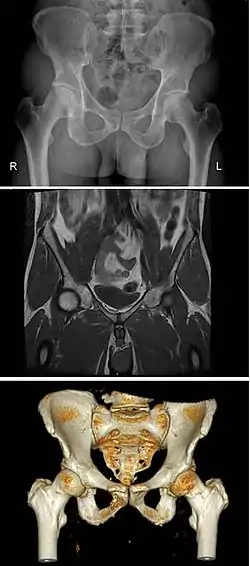

Pelvic cavity

|

|

|

The pelvic cavity is a body cavity that is bounded by the bones of the pelvis and which primarily contains reproductive organs and the rectum.

A distinction is made between the lesser or true pelvis inferior to the terminal line, and the greater or false pelvis above it. The pelvic inlet or superior pelvic aperture, which leads into the lesser pelvis, is bordered by the promontory, the arcuate line of ilium, the iliopubic eminence, the pecten of the pubis, and the upper part of the pubic symphysis. The pelvic outlet or inferior pelvic aperture is the region between the subpubic angle or pubic arch, the ischial tuberosities and the coccyx. [3]